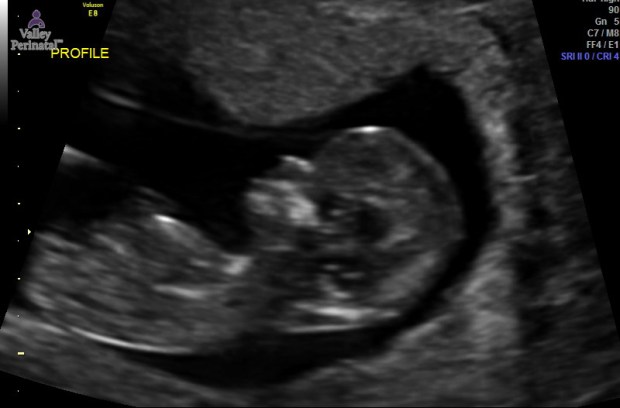

During our 12 week ultrasound the baby was very active! As soon as the ultrasound tech put the wand on my stomach, we could see the baby spinning and flipping around. We tried to get some close photos of baby’s face, but baby kept hiding behind his/her arms. We did, however, get a perfect profile picture of Baby Sells and I fell in love. I can’t wait to feel baby’s first move! We also got lucky at our 14 week checkup with an unexpected ultrasound! My doctor was training a new staff member and had her sit in on our appointment. She explained that 14 weeks is one of the best times to see a baby because of the development and space that there still is in the womb. She asked if I would be okay having an ultrasound done to show her. Uh yes, any chance we have to see our baby we’d take it! We walked into the ultrasound room and got ready to see our baby. Right away we saw baby stretched all the way out rolling around and waving his/her arms. Our doctor kept mentioning how long the baby’s legs were. The baby kept doing jump squats. I have a feeling once I can start feeling him/her, it’s going to be nonstop! Then, we saw the baby opening and closing it’s mouth. Our doctor said it was the baby drinking the amniotic fluid. It looked like like a little pac man. My heart just melted.

Baby Sells at 12 weeks.

Hi Baby!